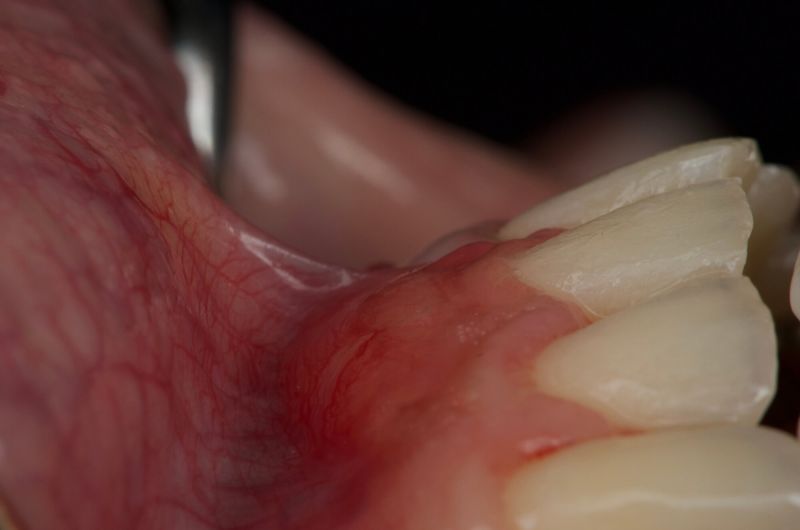

The patient was referred by the orthdontist for evaluation of their gum tissues, which showed signs of plaque accumulation, sensitivity, and gingival recession, particularly in the lower front teeth area. These issues needed to be addressed before proceeding with orthodontic treatment. The treatment plan was carried out in two phases. First, the patient underwent a thorough cleaning of their teeth and received detailed instructions on how to maintain good oral hygiene. Then, a free gingival graft was performed, where tissue was taken from the roof of the mouth and transplanted to the affected area, followed by sutures to secure it in place. As a result of these treatments, the patient experienced full coverage of the tooth roots, an increase in the amount of gum tissue, and improvement in tissue thickness, setting a solid foundation for their upcoming orthodontic treatment.